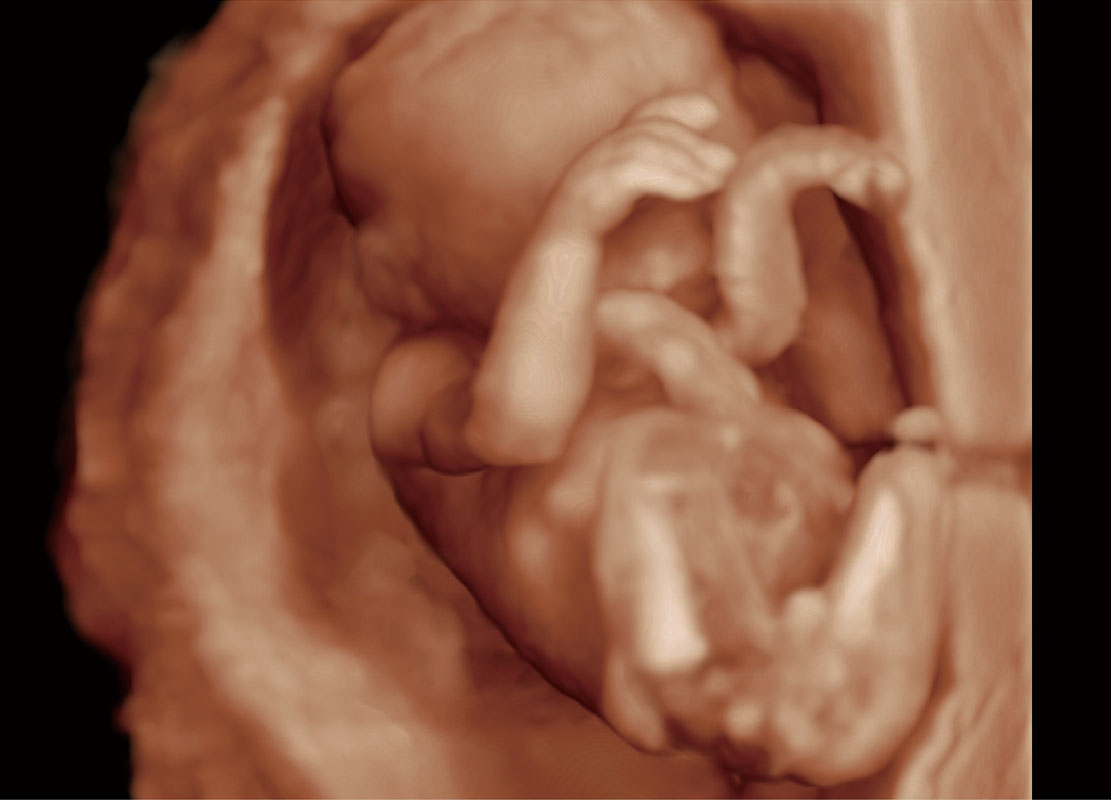

• 高分辨率容积成像-早孕胎儿

• 胎儿体循环